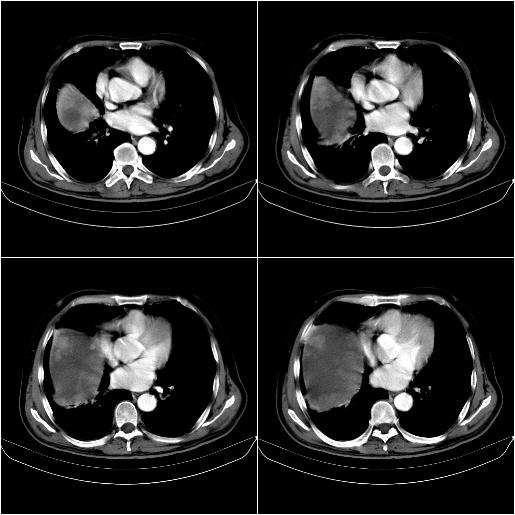

m,67y,肝癌9月,介入术后3月。现腹胀、纳差、腹泻。

1)肝癌介入治疗术后碘油沉积不良。2)门静脉瘤栓形成,腹膜广泛性转移。3)肝硬化,脾大,腹水。4)慢性胆囊炎。